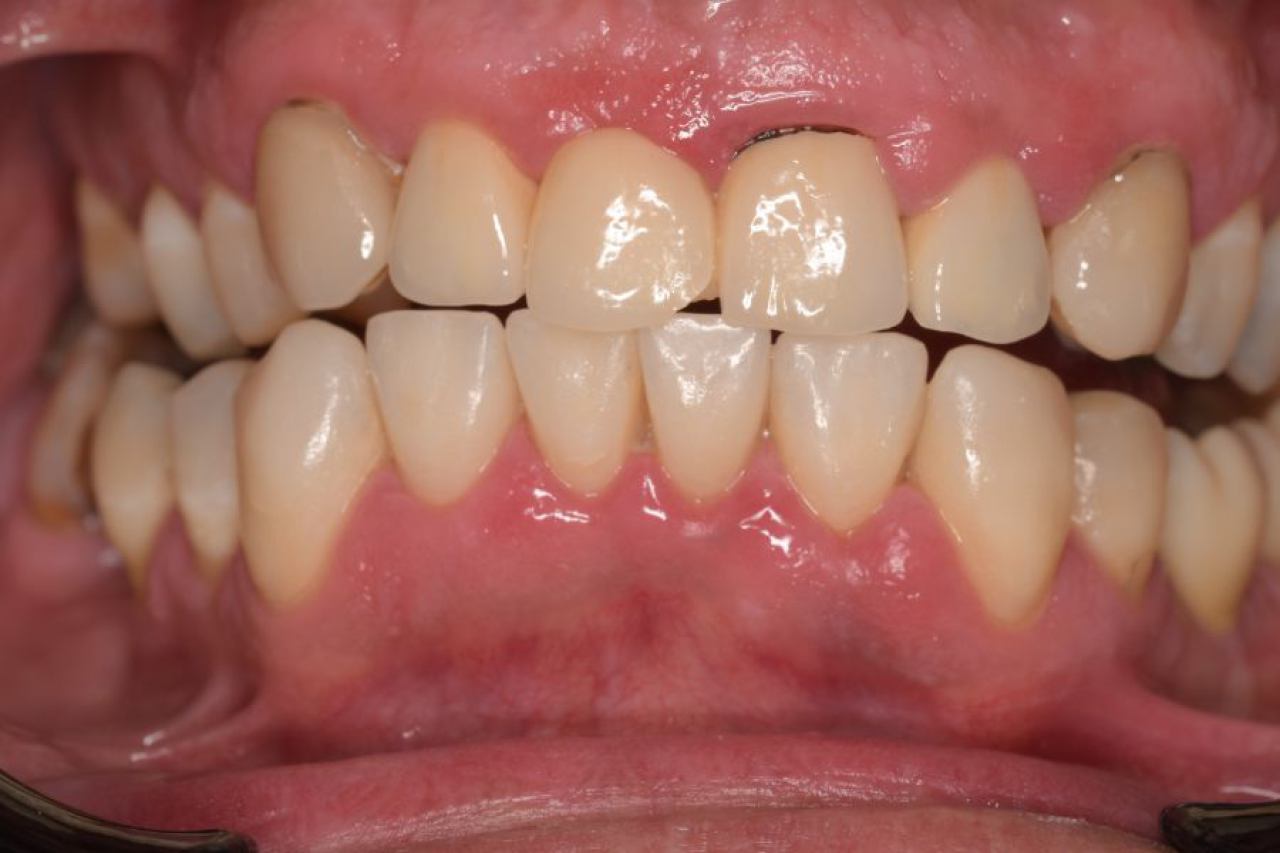

Implantologija - ugradnja dentalnih implantata

Dentalna implantologija je grana dentalne medicine koja objedinjuje znanje iz kirurgije, parodontologije i protetike i bavi se ugradnjom implantata u bezubu kost gornje ili donje čeljusti.

Marković Dental Clinic koristi najstariji, najistraživaniji i najkvalitetniji sustav dentalnih implantata Švedskog proizvođača Nobel Biocare.

All On 4 i All On 6 fiksni mostovi na 4-6 implantata, omogućavaju da se brzo, ekonomično i efikasno pacijentu od bezube čeljusti omogući mastikatorna i estetska funkcija.